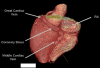

Background and objectives: While radiofrequency ablation catheter ablation of accessory pathways is generally safe and effective, anatomic variants can cause considerable challenges in effecting cure. Our objective was to use an unusual case where coronary sinus was absent and arterial venous fistula was present and a left-sided pathway required mapping and ablation to develop a framework to approach difficult cases.

Method: A detailed literature search and review of contemporary cardiac embryology was undertaken to attempt and to explain a common developmental anomaly. Adjunctive approaches during the ablation procedure, including intracardiac ultrasound, were used to guide mapping and ablation despite the lack of coronary sinus access.

Results: The accessory pathway was successfully ablated using a transseptal approach and intracardiac ultrasound guided mapping of the mitral annulus. A potential common mechanism to explain the apparently disparate anatomic variants in this patient was formulated.

Conclusions: Cardiac conduction development is complex and accessory pathway conduction may occur in the setting of arteriovenous anomalies thus providing insights as to the cause of WPW syndrome. Successful mapping and targeted ablation of left-sided pathways may be accomplished even when coronary sinus access is not possible.